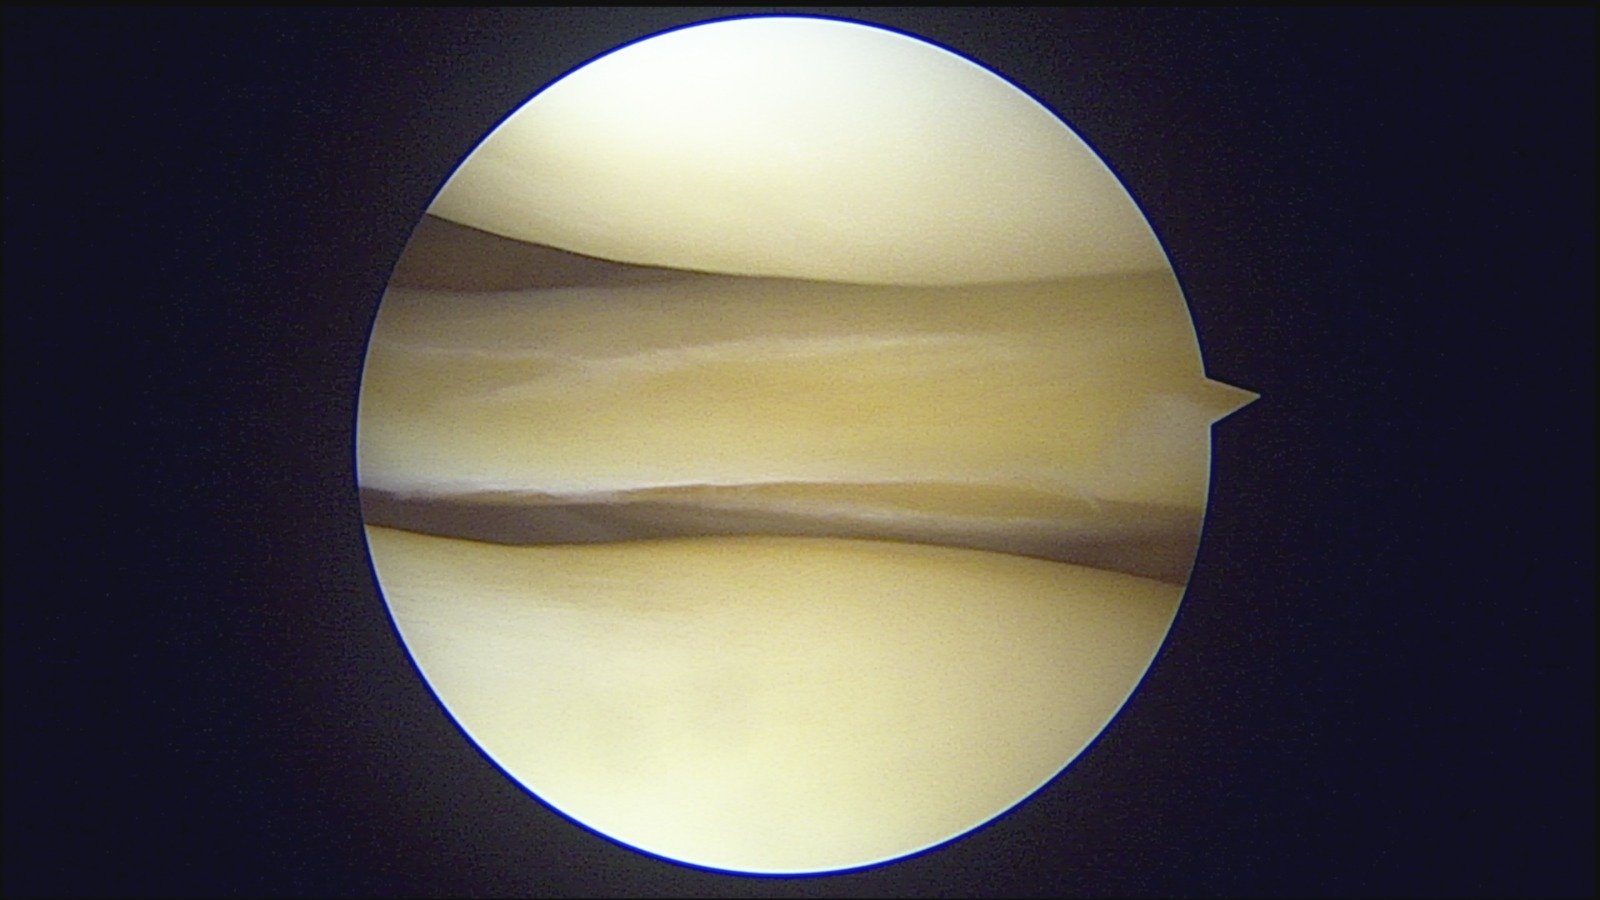

GalleryShoulder rotator cuff repair Meniscus root repair Meniscus repair Bankart repair for recurrent shoulder dislocation ACL reconstruction Machines Instruments